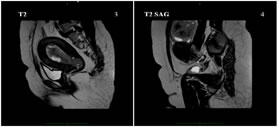

A 40 years old nulliparous premenopausal woman, presented to the gynaecology OPD with a chief complaint of abnormal uterine bleeding and pain in the lower abdomen, predominantly towards left side since an year. The patient had no significant relevant past history or risk factors. The clinical examination of the abdomen revealed no palpable mass. Abdominal ultrasound revealed a solid heterogeneously hypoechoic mass lesion arising from the left ovary, measuring approximately 55x53x50mm and showing moderate colour flow on colour doppler. A moderately enlarged uterus with increase in endometrial thickness was also identified (24 mm). No suspicious abdominal lymphadenopathy was noted. MRI Pelvis showed a single large well defined moderately enhancing, mixed predominantly solid lesion measuring approximately 60x58x53mm (MLXCCXAP) in the left adnexa, which is heterogeneously hypointense on T1W, Isointense with central hypointense areas on T2W, heterogeneously hyperintense with central hypointense areas on T2W/STIR and showing no restricted diffusion on DWI. Uterus appears moderately enlarged with multilobulated heterogenous diffuse moderately enhancing solid areas and non-enhancing cystic areas within the endometrial cavity. No suspicious pelvic lymphadenopathy was noted. Serum CA-125 concentration was elevated,95 U/mL (normal range <35 U/mL). After the positive frozen section pathological examination of the left ovary, the patient underwent a total abdominal hysterectomy, bilateral salpingo-oophorectomy, bilateral pelvic and para-aortic lymphadenectomy, and omentectomy. Pathological findings revealed a well-differentiated endometrioid carcinoma of the left ovary and a well-differentiated endometrioid carcinoma of the endometrium. The patient did not receive any adjuvant chemotherapy or radiotherapy and was suggested for a regular follow-up. Up to the last follow-up visit (April 2021), the patient had no recurrence.

Figure 1: Mixed predominantly solid, heterogeneously hypoechoic mass lesion in the left adnexa; Figure 2: Mass lesion showing moderate vascularity on application of colour Doppler; Figure 3: Increased endometrial thickness with multilobulated heterogenous diffuse solid areas and cystic areas; Figure 4: Few solid components showing mild vascularity on application of colour Doppler;